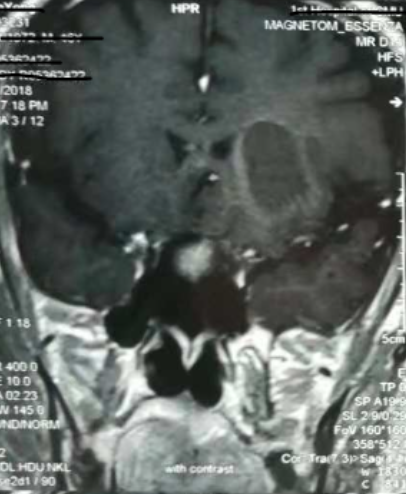

alt text

增強(qiáng)核磁提示:血腫液化周邊增強(qiáng)